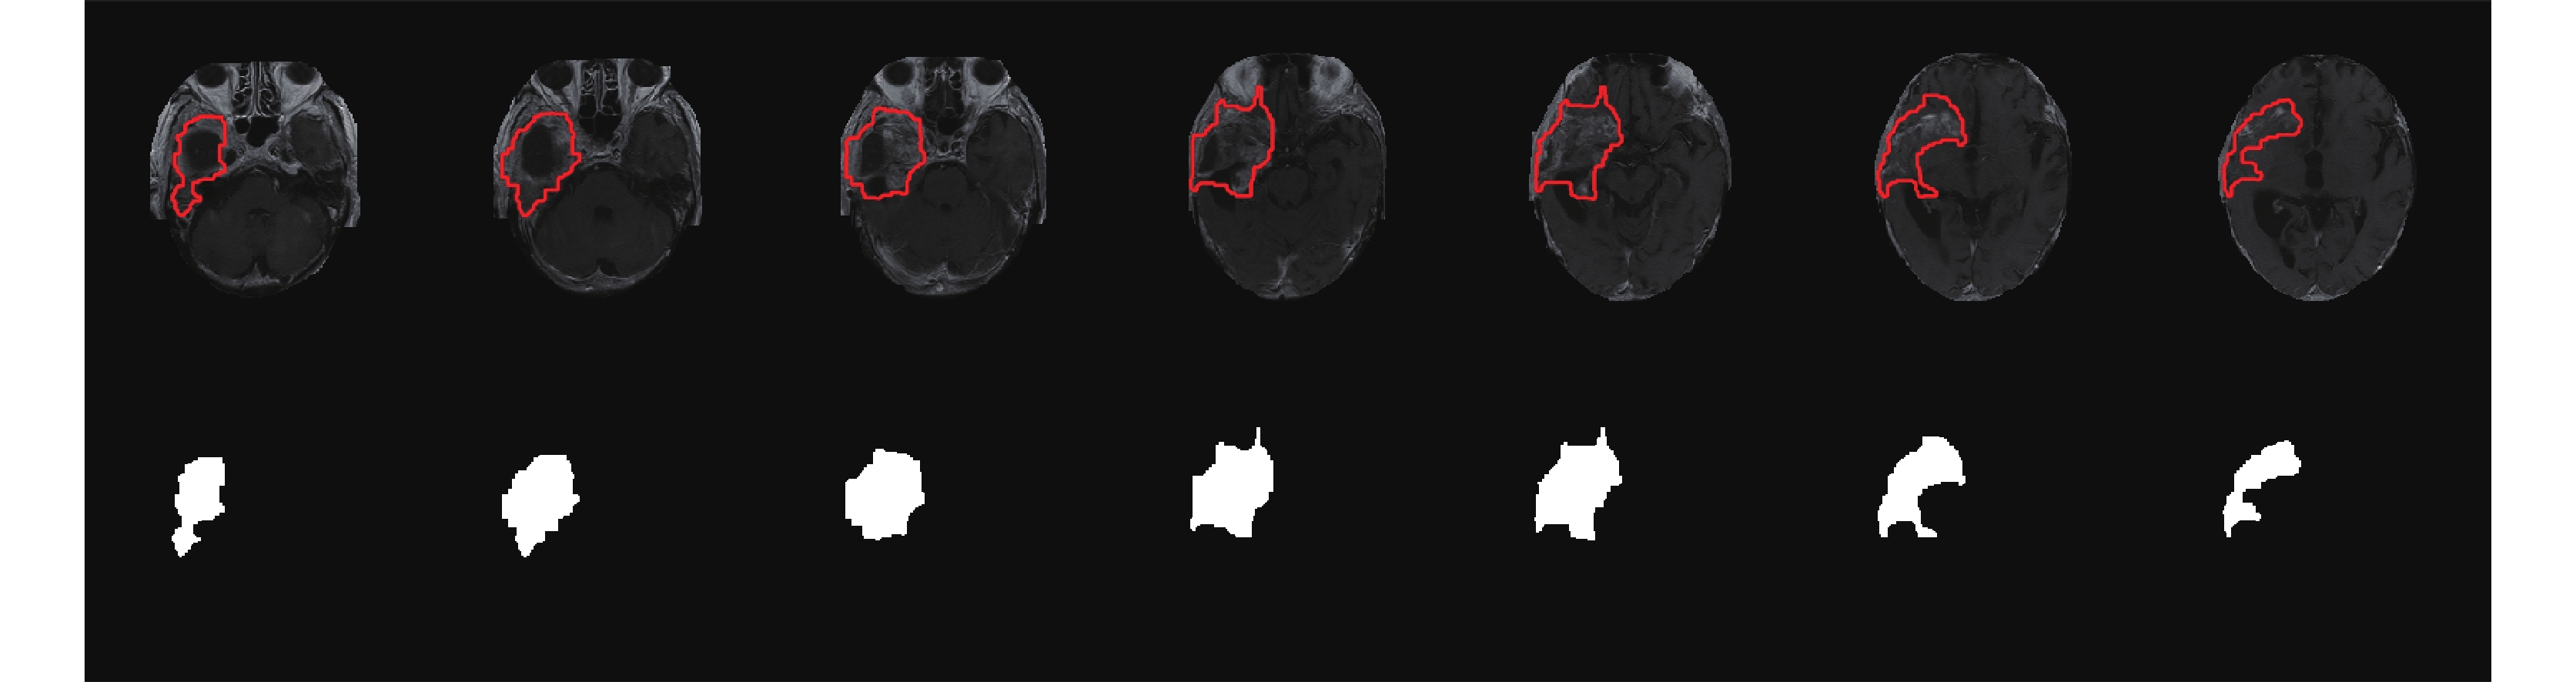

圖 1 為膠質瘤患者(60 歲,男性)T1 增強圖像利用卷積神經網絡分割的結果,第一行為剝去腦殼原圖,紅色封閉曲線內部為腫瘤部分,第二行為腫瘤區域對應標簽。此外,對于一些腫瘤區域較小的圖像,先由經驗豐富的醫生畫定感興趣區域(region of interest,ROI),然后再利用卷積神經網絡進行分割,以保證腫瘤分割的精度。